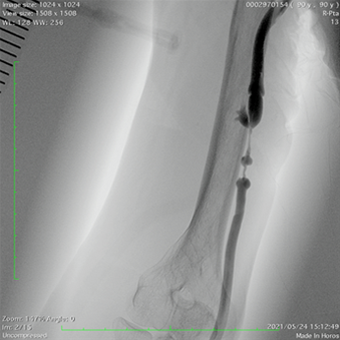

実際の症例②

人工血管静脈吻合部狭窄にて頻回に標準のバルーン拡張(PTA)を繰り返していましたが、ステントグラフト(ゴア社バイアバーン)留置にて狭窄消失しました。

狭窄は消失